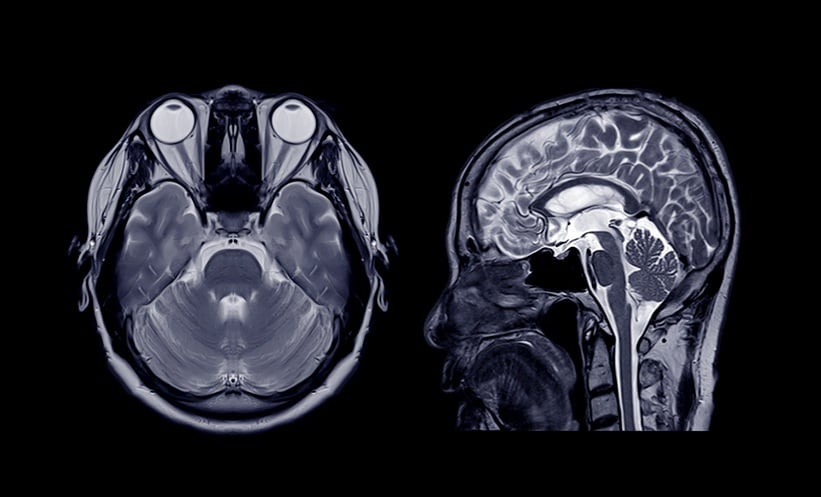

A NEW AI foundation model for neuroimaging was able to read and diagnose brain MRI scans in seconds, a 2026 health system-wide study has found.

The AI model was trained on more than 220,000 MRI studies and 5.6 million imaging sequences. It was then tested in a 1-year health system-wide study that included nearly 29,500 MRI studies.

Prima outperformed other advanced AI technologies, achieving a mean diagnostic area under the curve of 92% across 52 radiologic diagnoses from major neurologic disorders, including strokes, brain tumours, and haemorrhages. The model was able to identify neurologic conditions with an accuracy of up to 97.5%.